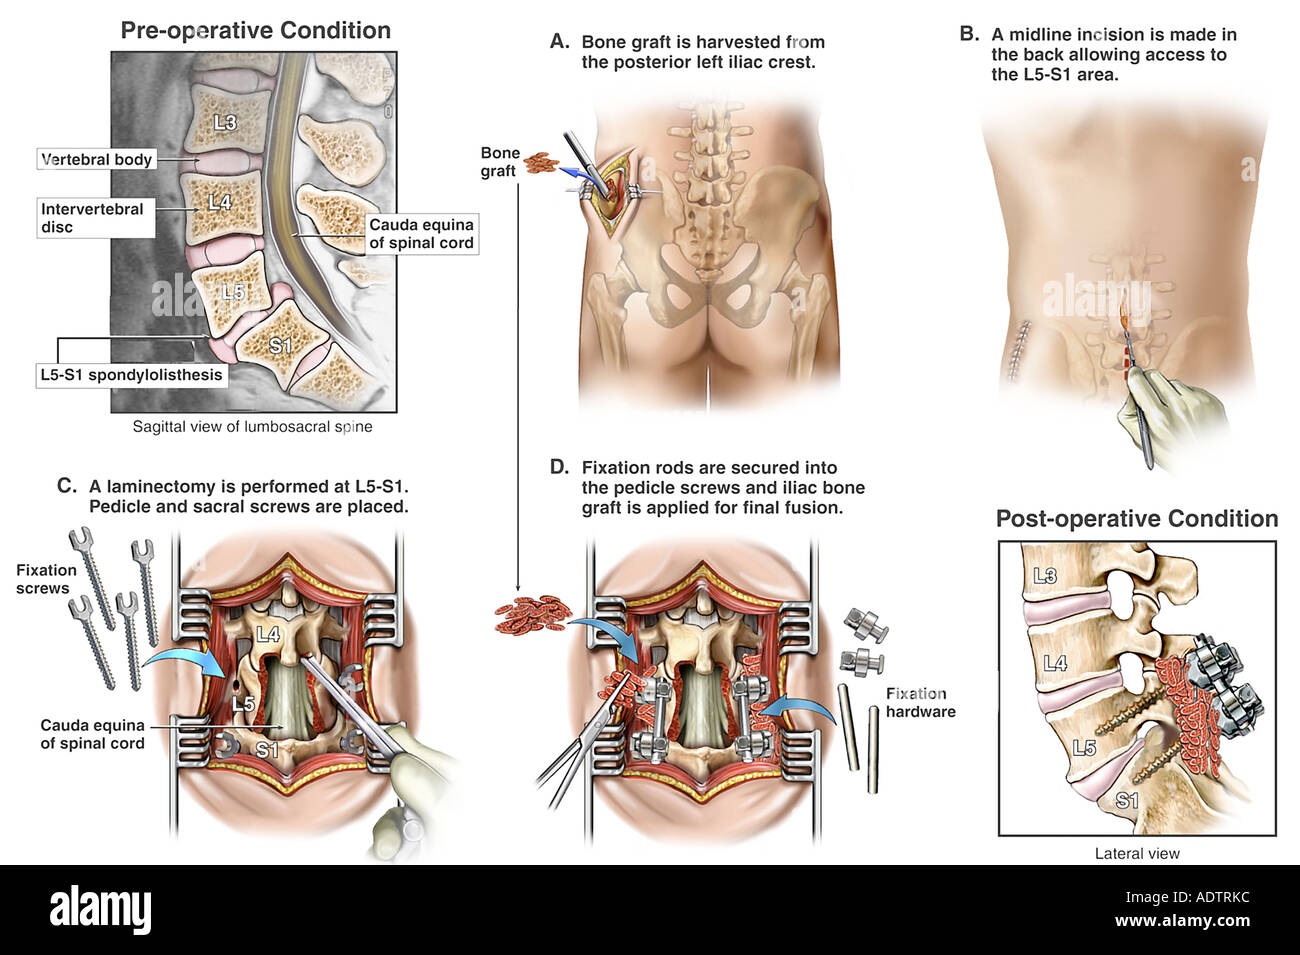

Spondylolyse et spondylolisthésis isthmique sont des aspects différents d’une affection dont la variabilité clinique est remarquable. Quantification du glissement. Clinique. Spondylolyse isthmique. Clinique. Imagerie. Formes cliniques. Indications thérapeutiques. Techniques chirurgicales.. La lyse se située plus souvent à l’étage L5/S1 mais peut parfois se retrouver à l’étage L4/L5. il est habituel que classer le glissement, occasionné par la lyse, en 4 stades de Meyerding. TRAITEMENT. Avant tout il est médical avec des antalgiques, de la rééducation associée au besoin à des infiltrations.

Benjiski Arthrodèse L4/L5/S1 les 10 et 18 octobre 2019 Page 3 Arthrodèse lombaire

Le spondylolisthésis implique habituellement les vertèbres L3-L4, L4-L5 ou le plus souvent L5-S1. Les types II (isthmique) et III (dégénératif) sont les plus fréquents.. Dans la majorité des cas, le spondylolisthésis concerne les vertèbres les plus basses, surtout au niveau de la jonction entre la colonne lombaire et le début de la colonne sacrée. La localisation entre la 4e et la 5e vertèbre lombaire est la plus commune : on parle de spondylolisthésis L4-L5.